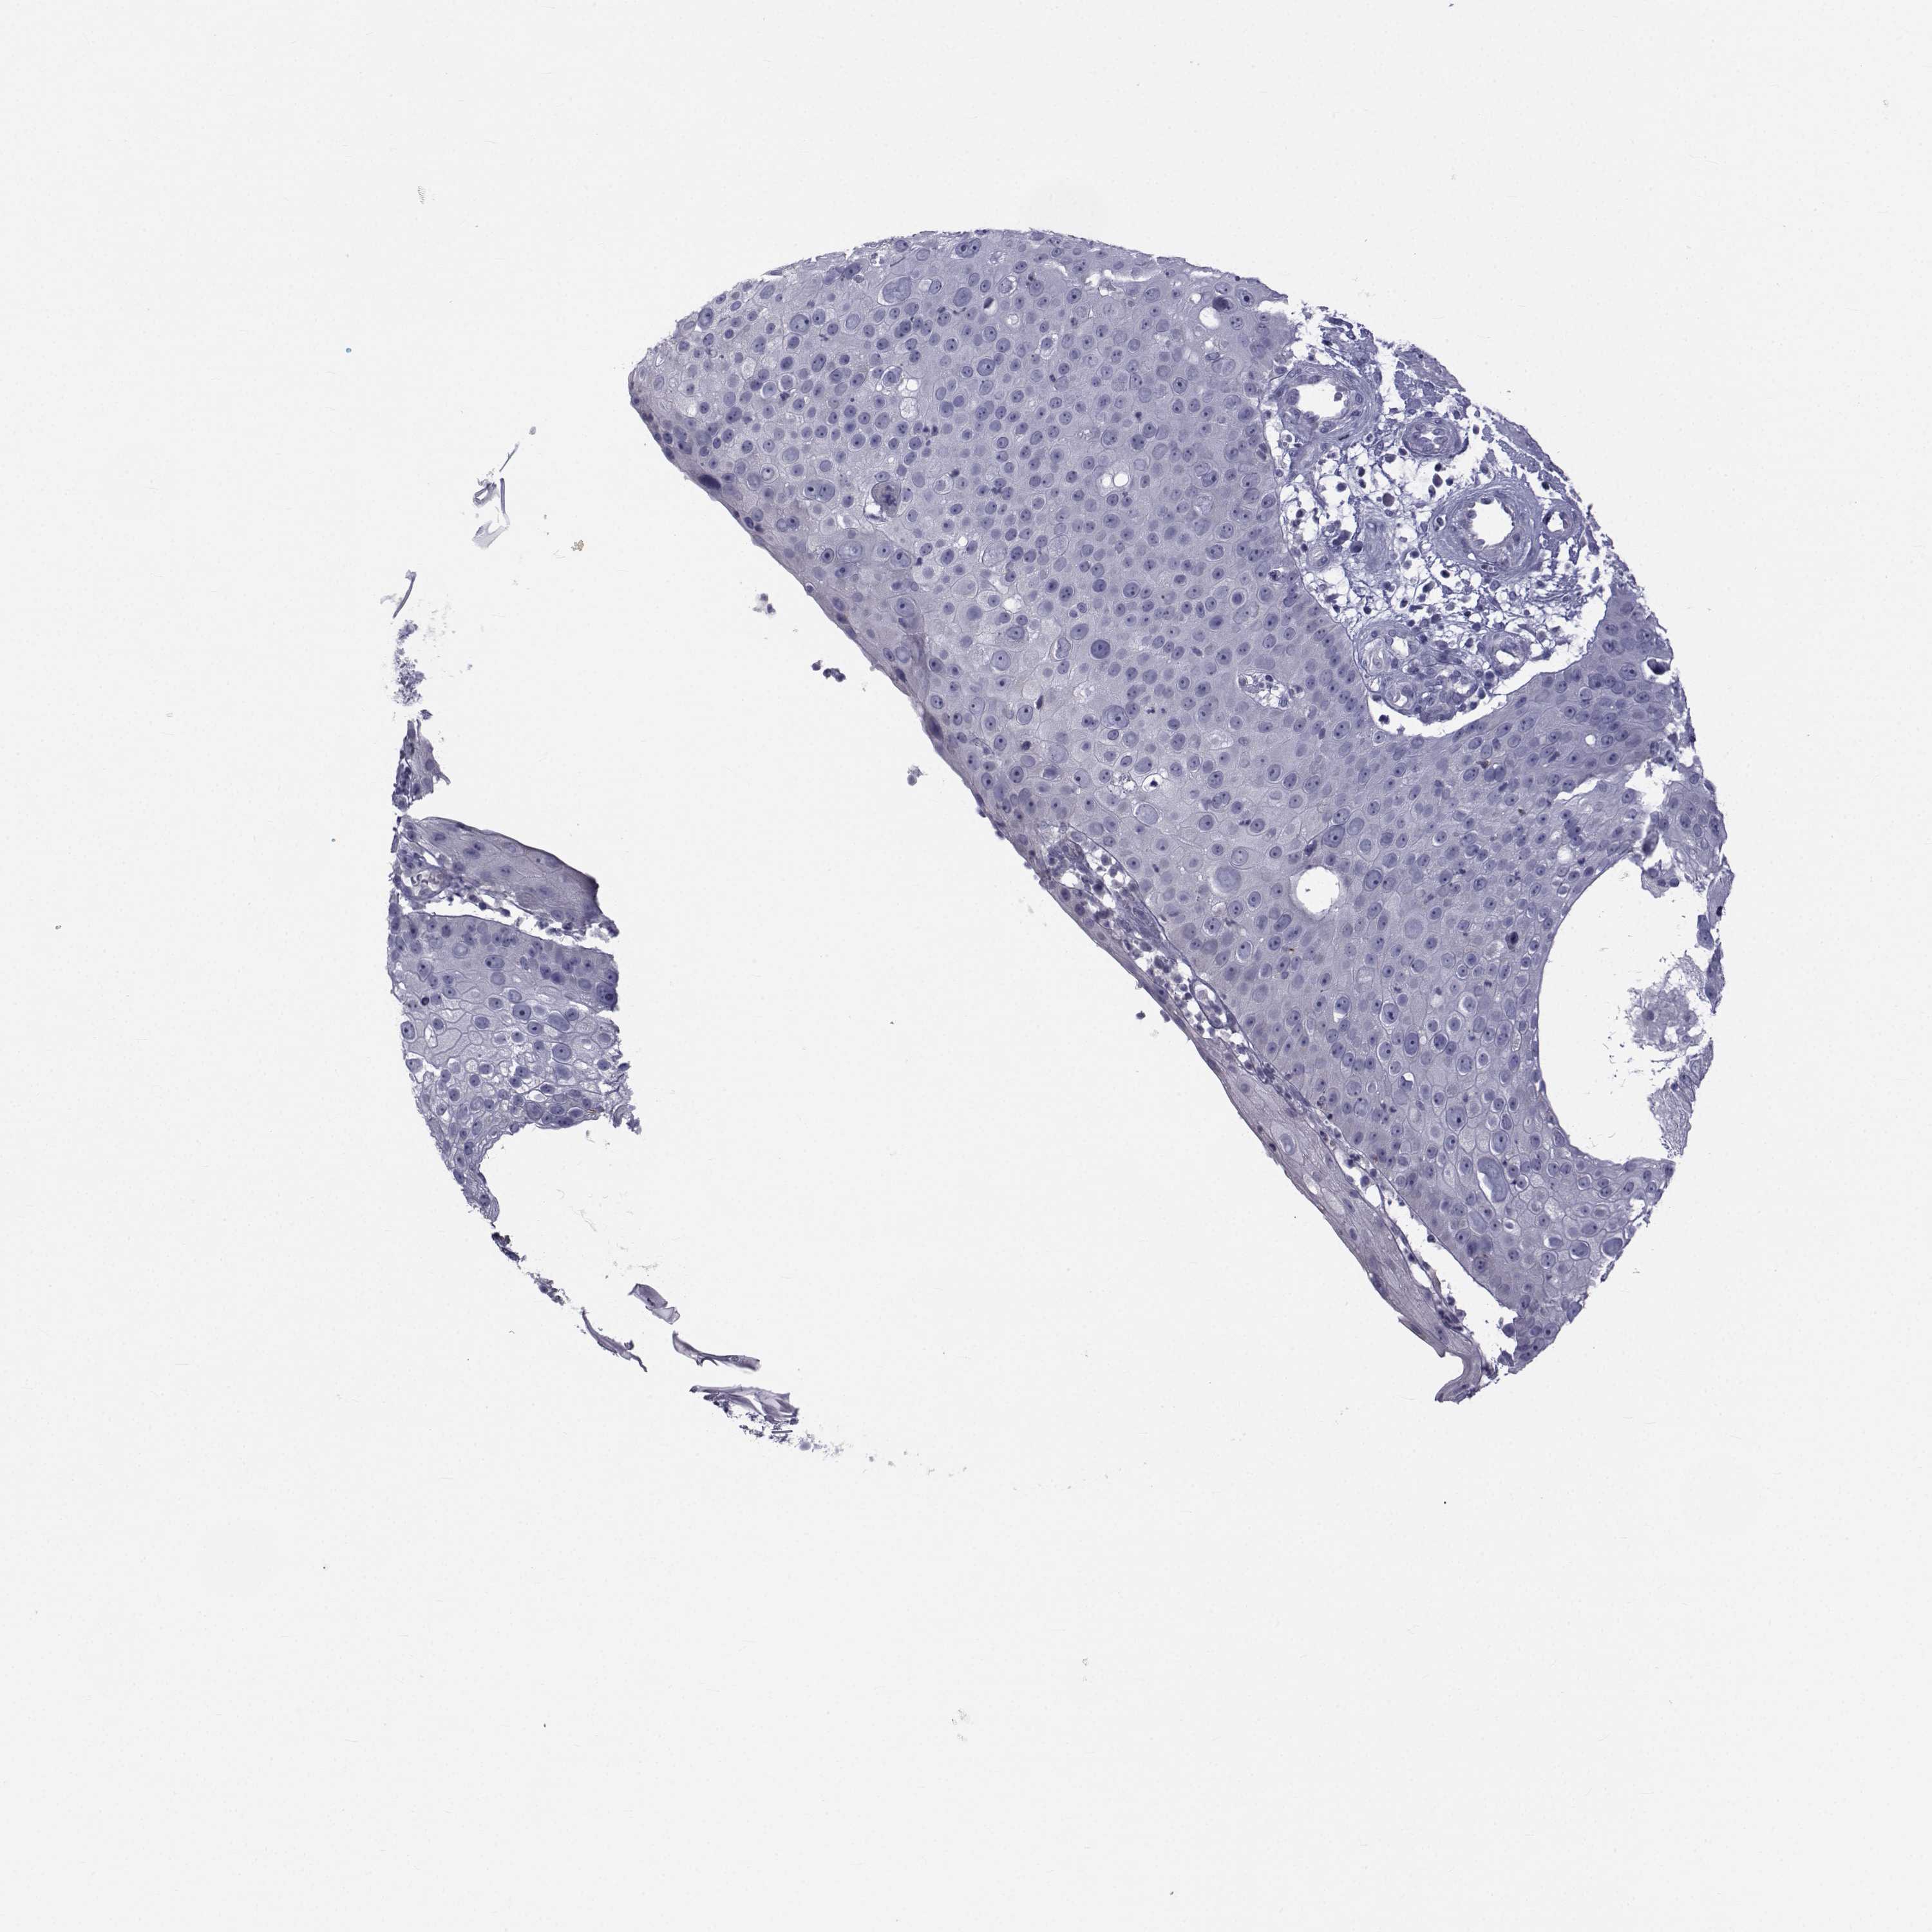

Basal cell and squamous cell cancer

SKIN CANCER - Protein expressioni

A mouse-over function shows sample information and annotation data. Click on an image to view it in a full screen mode. Samples can be filtered based on level of antibody staining by selecting one or several of the following categories: high, medium, low and not detected. The assay and annotation is described here.

Antibody stainingi

Antibody staining in the annotated cell types in the current human tissue is reported as not detected, low, medium, or high, based on conventional immunohistochemistry profiling in selected tissues. This score is based on the combination of the staining intensity and fraction of stained cells.

Each image is clickable and will lead to virtual microscopy that enables deeper exploration of all samples and also displays staining intensity scores, fraction scores and subcellular localization as well as patient and tissue information for each sample.

Antibody HPA044393

Antibody HPA053673

Antibody CAB009818

Staining

High

Medium

Low

Not detected

Intensity

Strong

Moderate

Weak

Negative

Quantity

>75%

75%-25%

<25%

None

Location

Nuclear

Cytoplasmic/membranous

Cytoplasmic/membranous,nuclear

Squamous cell carcinoma, NOS

Basal cell carcinoma